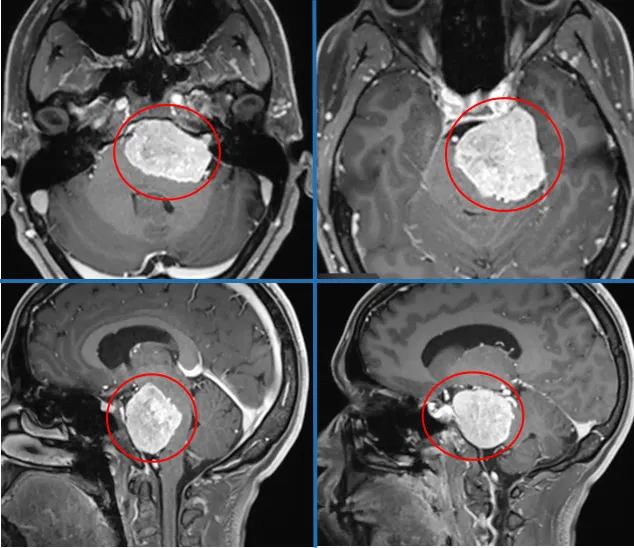

以下案例中的脑瘤是否体积巨大、位置不佳?岩斜区脑膜瘤,已挤压脑干。已知岩斜区脑膜瘤沿上2/3斜坡生长,位于颈静脉孔上方,岩斜区颅神经孔内侧。瘤体被脑干、基底动脉、III-VIII对颅神经、蝶鞍等众多神经血管结构紧密包围,该部位难以接近,手术入路设计尤为困难。

随着岩斜区脑膜瘤持续生长,可将脑干向后方及对侧推挤,与基底动脉分支和穿支血管关系密切,瘤体侧方常被颅神经遮盖,肿瘤累及海绵窦的情况常见。由于瘤体毗邻的颞骨解剖结构复杂,导致该部位肿瘤被多个易损结构包绕,手术难度极高。

术前MRI显示肿瘤范围及与周边结构关系。